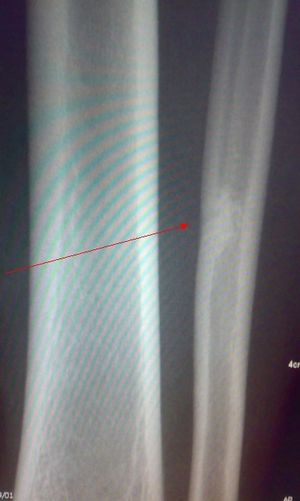

标题: X7846:M 20岁 外伤来诊。良性骨肿瘤吗? [打印本页]

标题: X7846:M 20岁 外伤来诊。良性骨肿瘤吗?

局限性骨皮质缺损愈合修复后改变。

考虑腓骨下段良性骨肿瘤或骨肿瘤样病变(软骨瘤?);建议行mri检查。

我考虑是非骨化性纤维瘤愈合期。

考虑为腓骨内髓质型的nof。

腓骨中下段骨皮质下不规则高密度影,侧位呈水滴形。外伤,估计平时没有症状,结合病人年龄,支持纤维性骨皮质缺损